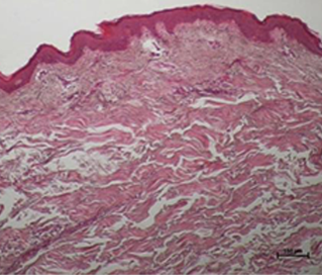

눈으로 직접 확인하는

콜라겐 활성 변화

온다리프팅 시술 후 진피의 콜라겐이 활성화 되고

늘어져 있던 콜라겐이 수축되는 것을 알 수 있습니다.

스킨타이트닝과 리프팅 효과가 동시에 이루어져

만족스러운 피부 리모델링이 이루어집니다.

*진피의 콜라겐(분홍색 영역) 활성화